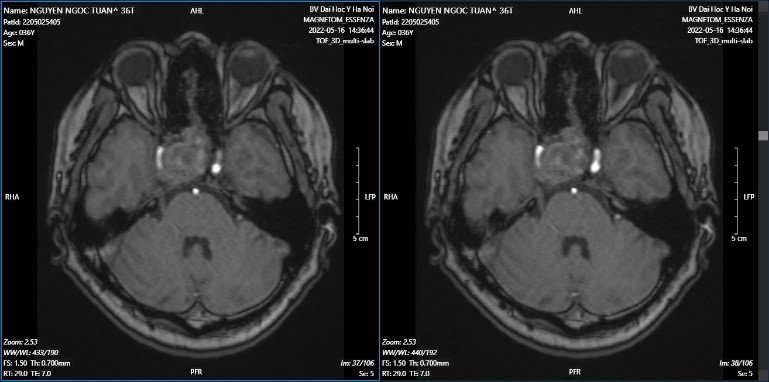

Hình ảnh MRI ngày 16/5, khối tăng tỉ trọng vùng yên và trên yên, kích thước 31 x 32 x 46mm, có chảy máu bên trong khối u, khối xâm lấn giao thoa thị giác, xoang hang bên phải, ôm quanh gây hẹp lòng động mạch cảnh trong bên phải đoạn xoang hang.

Hình ảnh MRI sọ (19/05): Tổn thương ở thùy trán, thùy thái dương và thùy đỉnh phải thuộc vùng cấp máu của động mạch não giữa phải, gây hiệu ứng khối nhiều xung quanh. Trên chuỗi xung mạch TOF, động mạch cảnh trong phải nhỏ, bị đè ép bởi khối u, không thấy tín hiệu dòng chảy ở đoạn siphon động mạch cảnh trong, động mạch não giữa phải đoạn M1 nhỏ, các đoạn còn lại động mạch não giữa không thấy hẹp tắc.

Khối u tuyến yên xâm lấn giao thoa thị giác, xoang hang phải và xoang bướm, chèn ép hẹp nhiều động mạch cảnh trong phải, không đánh giá được dòng chảy ở đoạn siphon